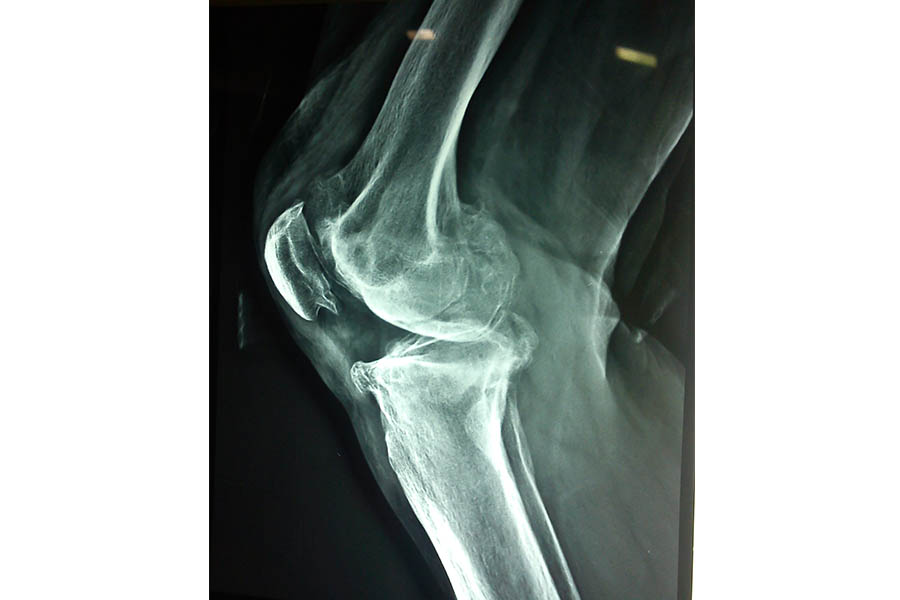

Cold Orthopaedics

Case 1